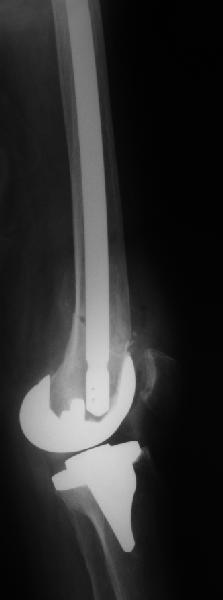

То, что планируется - наиболее распространенный подход. Еще менее инвазивный вариант - закрытый антеградный интрамедуллярный остесинтез. Мы используем гвозди, которые выпускаются предприятием ЦИТО, т.е. недорогие. Там в дистальное отверстие можно ввести 3 винта (2 снаружи и один навстречу), еще и угловая стабильность получается.